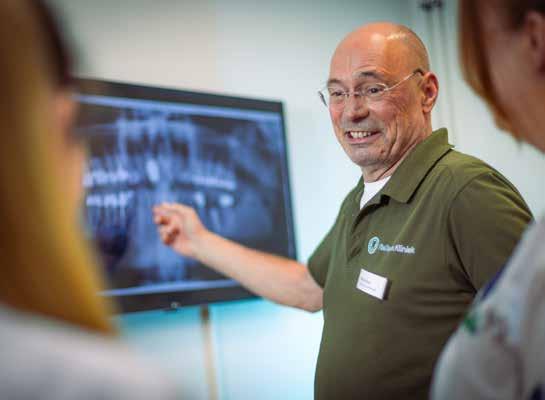

56 GEBIT MET KARAKTER

Bij VieDenta Kliniek in Nieuw-Bergen en Oirschot streven ze een gebit met karakter na.